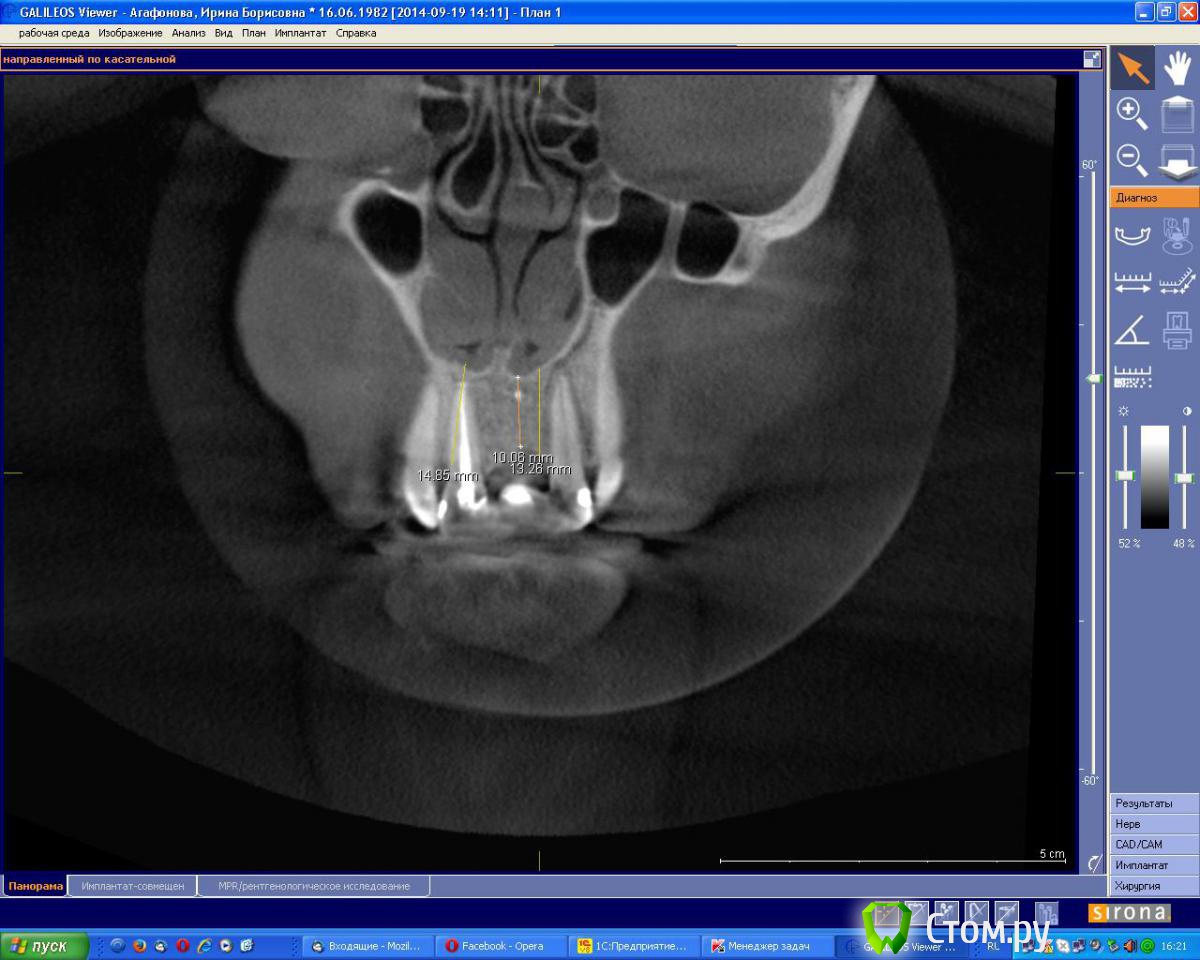

an_ver Опубликовано 19 сентября, 2014 Поделиться Опубликовано 19 сентября, 2014 (изменено) Молодая девушка,ранее был удален 21..с ее слов после удаления началось воспаление,выводили 2 месяца.После удаления-выведения прошло 6 месяцев. Сейчас фиксирован адгезивный мост. Вот такую картину имеем на сегодня. Что посоветуете,коллеги.Девушка хочет зуб Изменено 19 сентября, 2014 пользователем an_ver Ссылка на комментарий

an_ver Опубликовано 2 октября, 2014 Автор Поделиться Опубликовано 2 октября, 2014 Пики есть, уровень тоже. Согласен с Alexey Dok и faity, тут любая техника сработает от мембранной до ламината. Если эстетика немаловажна - VIP-CT или чего попроще.VIP на графт,сверху мембрану? Ссылка на комментарий